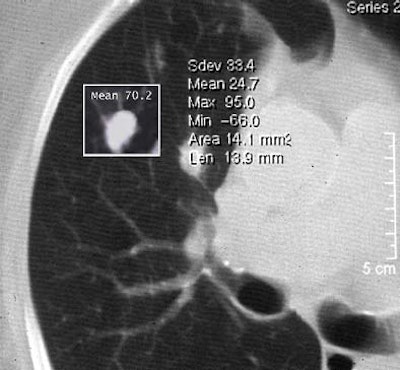

For example, a nodule should generally be biopsied if its attenuation is 15 HU or higher following contrast administration, Yankelevitz said. But the rule doesn't work well when nodules are smaller than 1 cm.

| Non-solid nodule pre- and post-contrast. |

| Volumetric analysis of nodule size shows a doubling rate of greater than 750 days. |